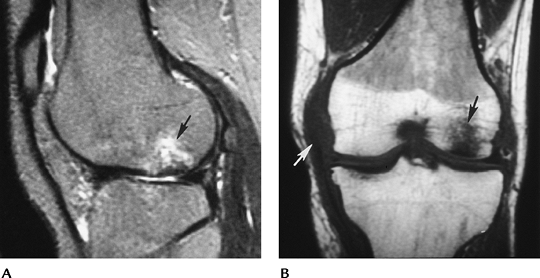

![]() |

FIGURE 5-58 MR images of osteochondritis dissecans in two different patients. T2-weighted sagittal (A) and axial (B) images showing a large defect with high-intensity fluid (arrows) separating the fragment from the condyle. This is an unstable lesion. (C) Sagittal T2-weighted image in a different patient showing abnormal signal intensity (arrows), no fluid line around the lesion, and intact cartilage. This is a stable lesion.